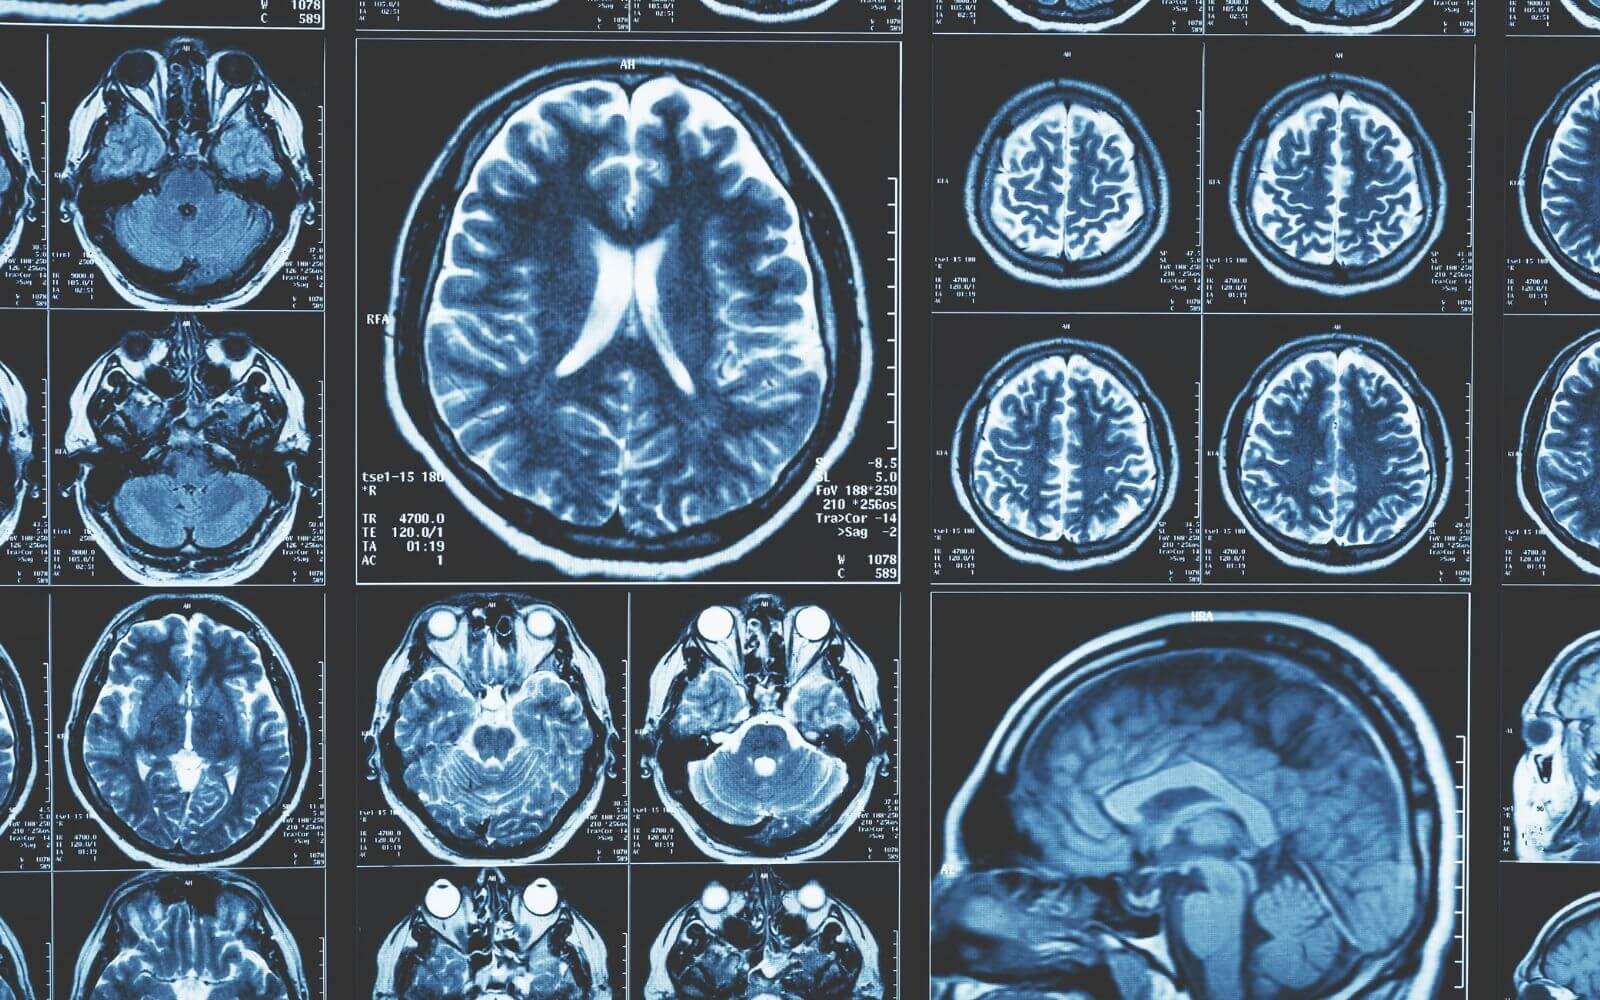

An interim report of a clinical trial of intracerebral injection of stem cells adds to a growing body of evidence supporting safety and efficacy of stem cell therapy for stroke.  A clinical team led by Dr. Gary Steinberg at Stanford University Medical Center reported results from 16 patients who received stereotactic injections into damaged brain regions consisting of MSCs that were modified to facilitate their differentiation into neural stem cells. A single injection of 2.5 million, 5 million or 10 million stem cells (without a dose-response) resulted in significant improvement as measured by standard functional impairment scales within one month of injection that grew & persisted throughout a one-year period. The few adverse events were related to the surgical procedure, not the cellular treatment (1).   Functional recoveries were quite striking, including patients who had stroke events three years previously who were able to walk following the stem cell injection while previously being wheel-chair-bound.